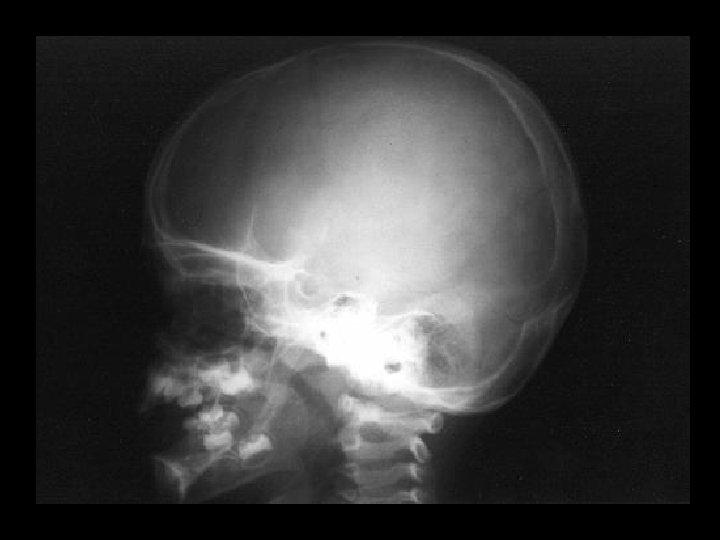

Renal osteodystrophy • Findings: – Diffuse skull uptake – Plain film shows a granular appearance = "salt & pepper" • ddx: – Mets (prostate, breast, lung, lymphoma, bladder) – Metabolic bone disease (hyperpara, osteomalacia, rickets, hyp vit D) – Paget's disease – Myelofibrosis – Mastocytosis – Aplastic anemia